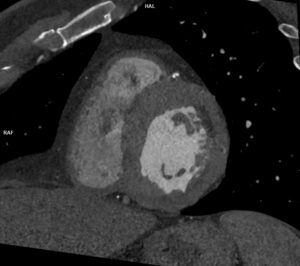

Video 1: reconstrucție cine în planul valvei aortice din achiziție angioCT coronariană cu sincronizare ECG cu evidențierea valvei aortice morfologic tricuspide, funcțional bicuspide prin fuziunea cuspelor pentru sinusul Valsalva drept şi sinusul non-coronarian, la nivelul fuziunii fiind prezente calcificări.

Discuţie caz nr 128: Valva aortică este bicuspidă prin coaptarea cuspei pentru sinusul Valsalva drept și cuspei pentru sinusul non-coronarian, la nivelul cooptării fiind prezenta o calcificare. Secundar valvei aortice bicuspide se remarca creștere de calibru a aortei ascendente, acesta fiind și motivul îndrumării pacientului la examinare CT de aortă toracică – examinare care ar trebui sa fie efectuată obligatoriu cu sincronizare ECG. Întâmplător, la limita inferioară a câmpului de scanare, la nivelul arterei mezenterice superioare se evidențiază un fald de disecție cu ambele lumene circulante.